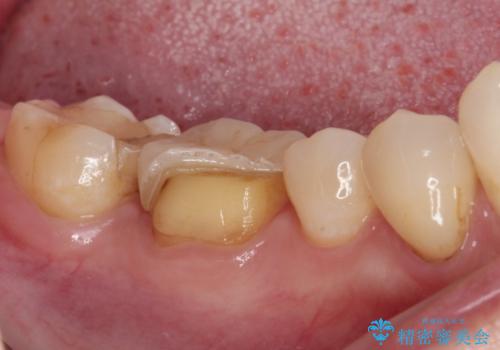

- セラミッククラウンが度々欠けてしまうとのことで来院された患者様です。

セラミッククラウンを装着するには、削る量がやや少ない印象であったので、クラウン破折リスクを回避するために削る量を少し増やすこととしました。

また、咬合力が強いため、強化セラミックのみで製作するフルジルコニアクラウンにて補綴治療することとしました。